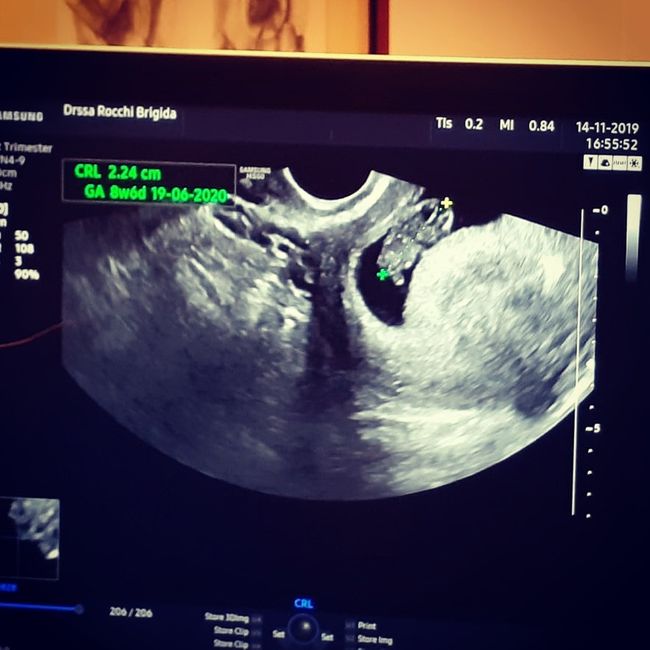

Eccolo il mio piccolissimo fagiolino, di cui sono già follemente innamorata Ieri prima visita!La dottoressa mi ha detto che dovrei essere di 8 settimane ma il feto è più piccolo e corrisponde a 6 settimane... è la mia prima gravidanza e...